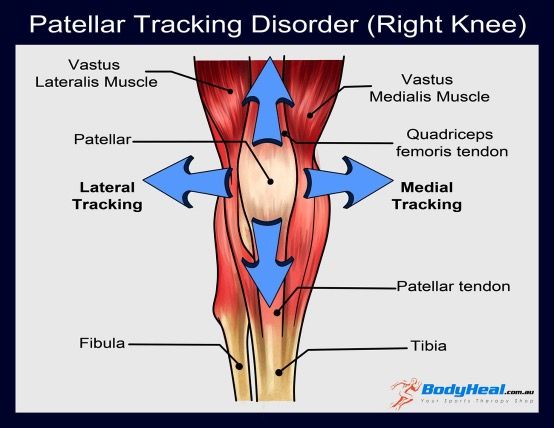

What is Patella Tracking Syndrome

What is Patella Tracking Syndrome

Your knee has many working parts which include bones, ligaments, cartilage and meniscus. The patella sits in front of your knee and it helps give the joint structure and strength, allowing you to bend the knee. Due to the load and forces that each knee absorbs with day-to-day activity, it is important to ensure that there is good biomechanics in the knees.

The patella sits in a groove on top of the femur which is lined by cartilage allowing it to glide along the groove with movement. The patella is encapsulated by a large tendon with ligaments supporting it on the side. When the patella has altered tracking, it doesn’t move smoothly in the groove and shifts too far to the outside of the leg. It can also shift towards the inside of the leg. This can occur from several different causes including:

- Traumatic injury to the knee

- Repetitive twisting movements of the knee

- Weak thigh muscles

- Muscles, tendons or ligaments in the leg that are too tight or loose

Symptoms of patella tracking syndrome include pain at the front of the knee. This can be felt going downstairs. A feeling of popping, grinding or locking in the knee or a feeling as if your knee won’t hold your weight are associated complaints.

Treatment involves improving the biomechanics of the knee and identifying the causative factor. It may also involve strengthening the muscles in the leg.